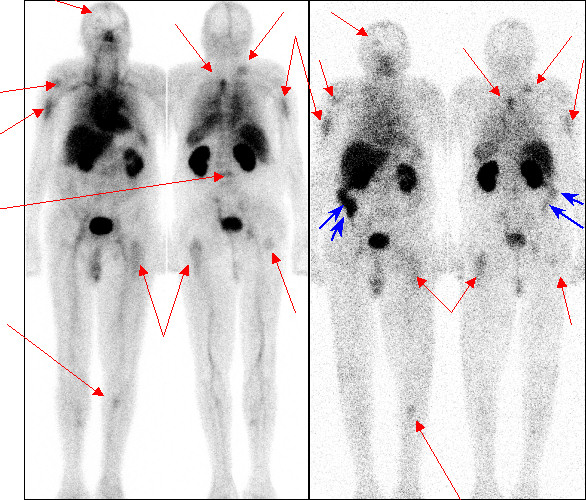

08.-09. 11. 2004 CEA-Scan:

/Obr. č.2: celotělová scintigrafie - CEA-Scan v AP a PA projekcích,

vlevo - 5 hodin po aplikaci, vpravo - 24 hodin po aplikaci 99mTc CEA-Scan/

Provedeny celotělová vyšetření v AP a PA projekcích 5 (trvání záznamu 25 min) a 24 hodin (trvání záznamu 35 min) po aplikaci 800 MBq preparátu

CEA-Scan (Immunomedics). Gama kamera Picker Prism XP 2000, kolimátory

LEHR. Doplněno SPECT vyš. 5 hodin po aplikaci -

dráha rotace 360 st., úhel rotace 3 st., počet kroků 60, trvání kroku 30 se. Kolimátory

LEHR, gama kamera Picker Prism XP 2000.

Nález:

Mnohočetné, CEA produkující metastázy (červené šipky) ve skeletu, patrné již při scintigrafii skeletu

17.06. 2004, dnes navíc i ložisko vpravo frontálně. Na pozdních snímcích za 24 hodin po aplikaci se zobrazuje ostře ohraničené, poměrně veliké ložisko patologické kumulace (modré šipky) značené

anti-CEA protilátky v obl. odpovídající zřejmě ascendentu, v rozsahu asi 10 cm - infiltrativní či extralumární růst? - zřejmě primární tumor.

Obrázky č. 3a-c dokumentují v.s. metastatické postižení skeletu, korelující s nálezem při celotělové scintigrafií skeletu (viz

obr.1 - žluté šipky), avšak s kumulací značené anti-CEA protilátky v těchto ložiscích.